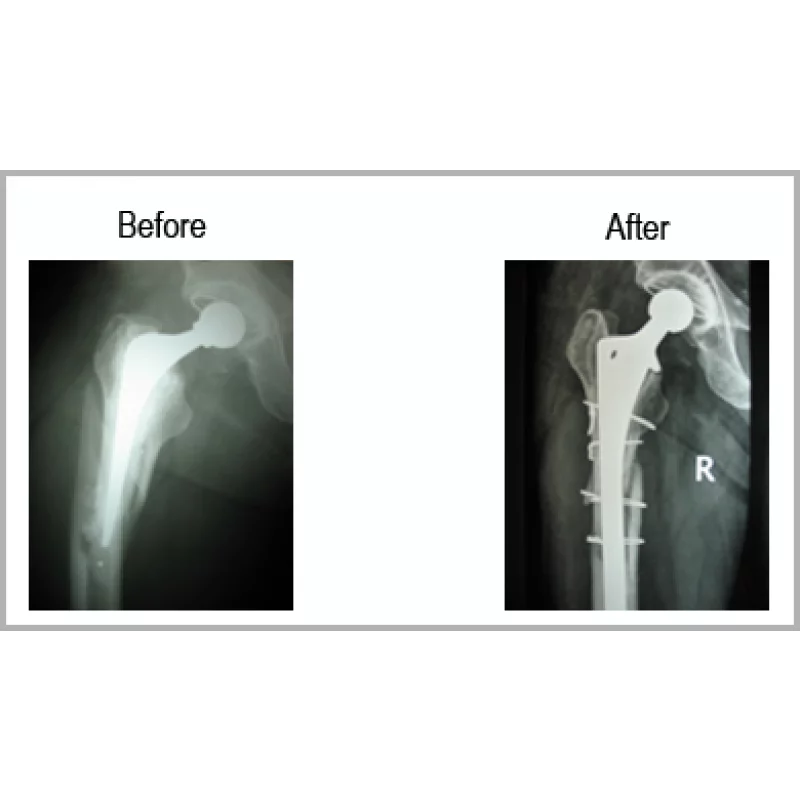

Total Hip Implant In Place With Fracture Femur

A Male Aged 63 Years Was Operated For Right Total Hip Replacement. He Met With An Accident. He Fractured His Thigh Bone-femur With Total Hip Implant In Place.He Underwent Revision Of Femoral Component With Special Implant With Wiring Of The Fracture. Now He Is Walking Normally Without Any Type Of Discomfort.... Read more